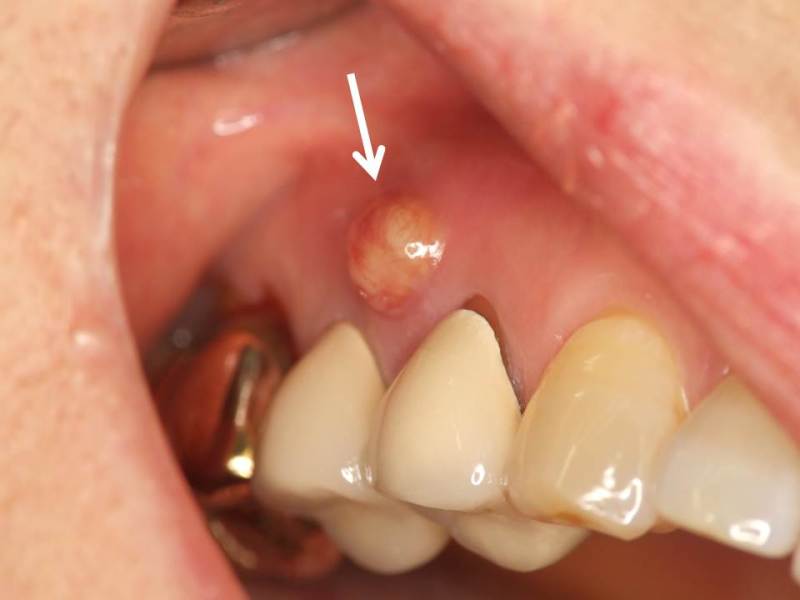

また神経が死んでしまって、根っこの先に膿作ります。

これが活発になって、急性症状を起こすとめちゃくちゃ痛いです。